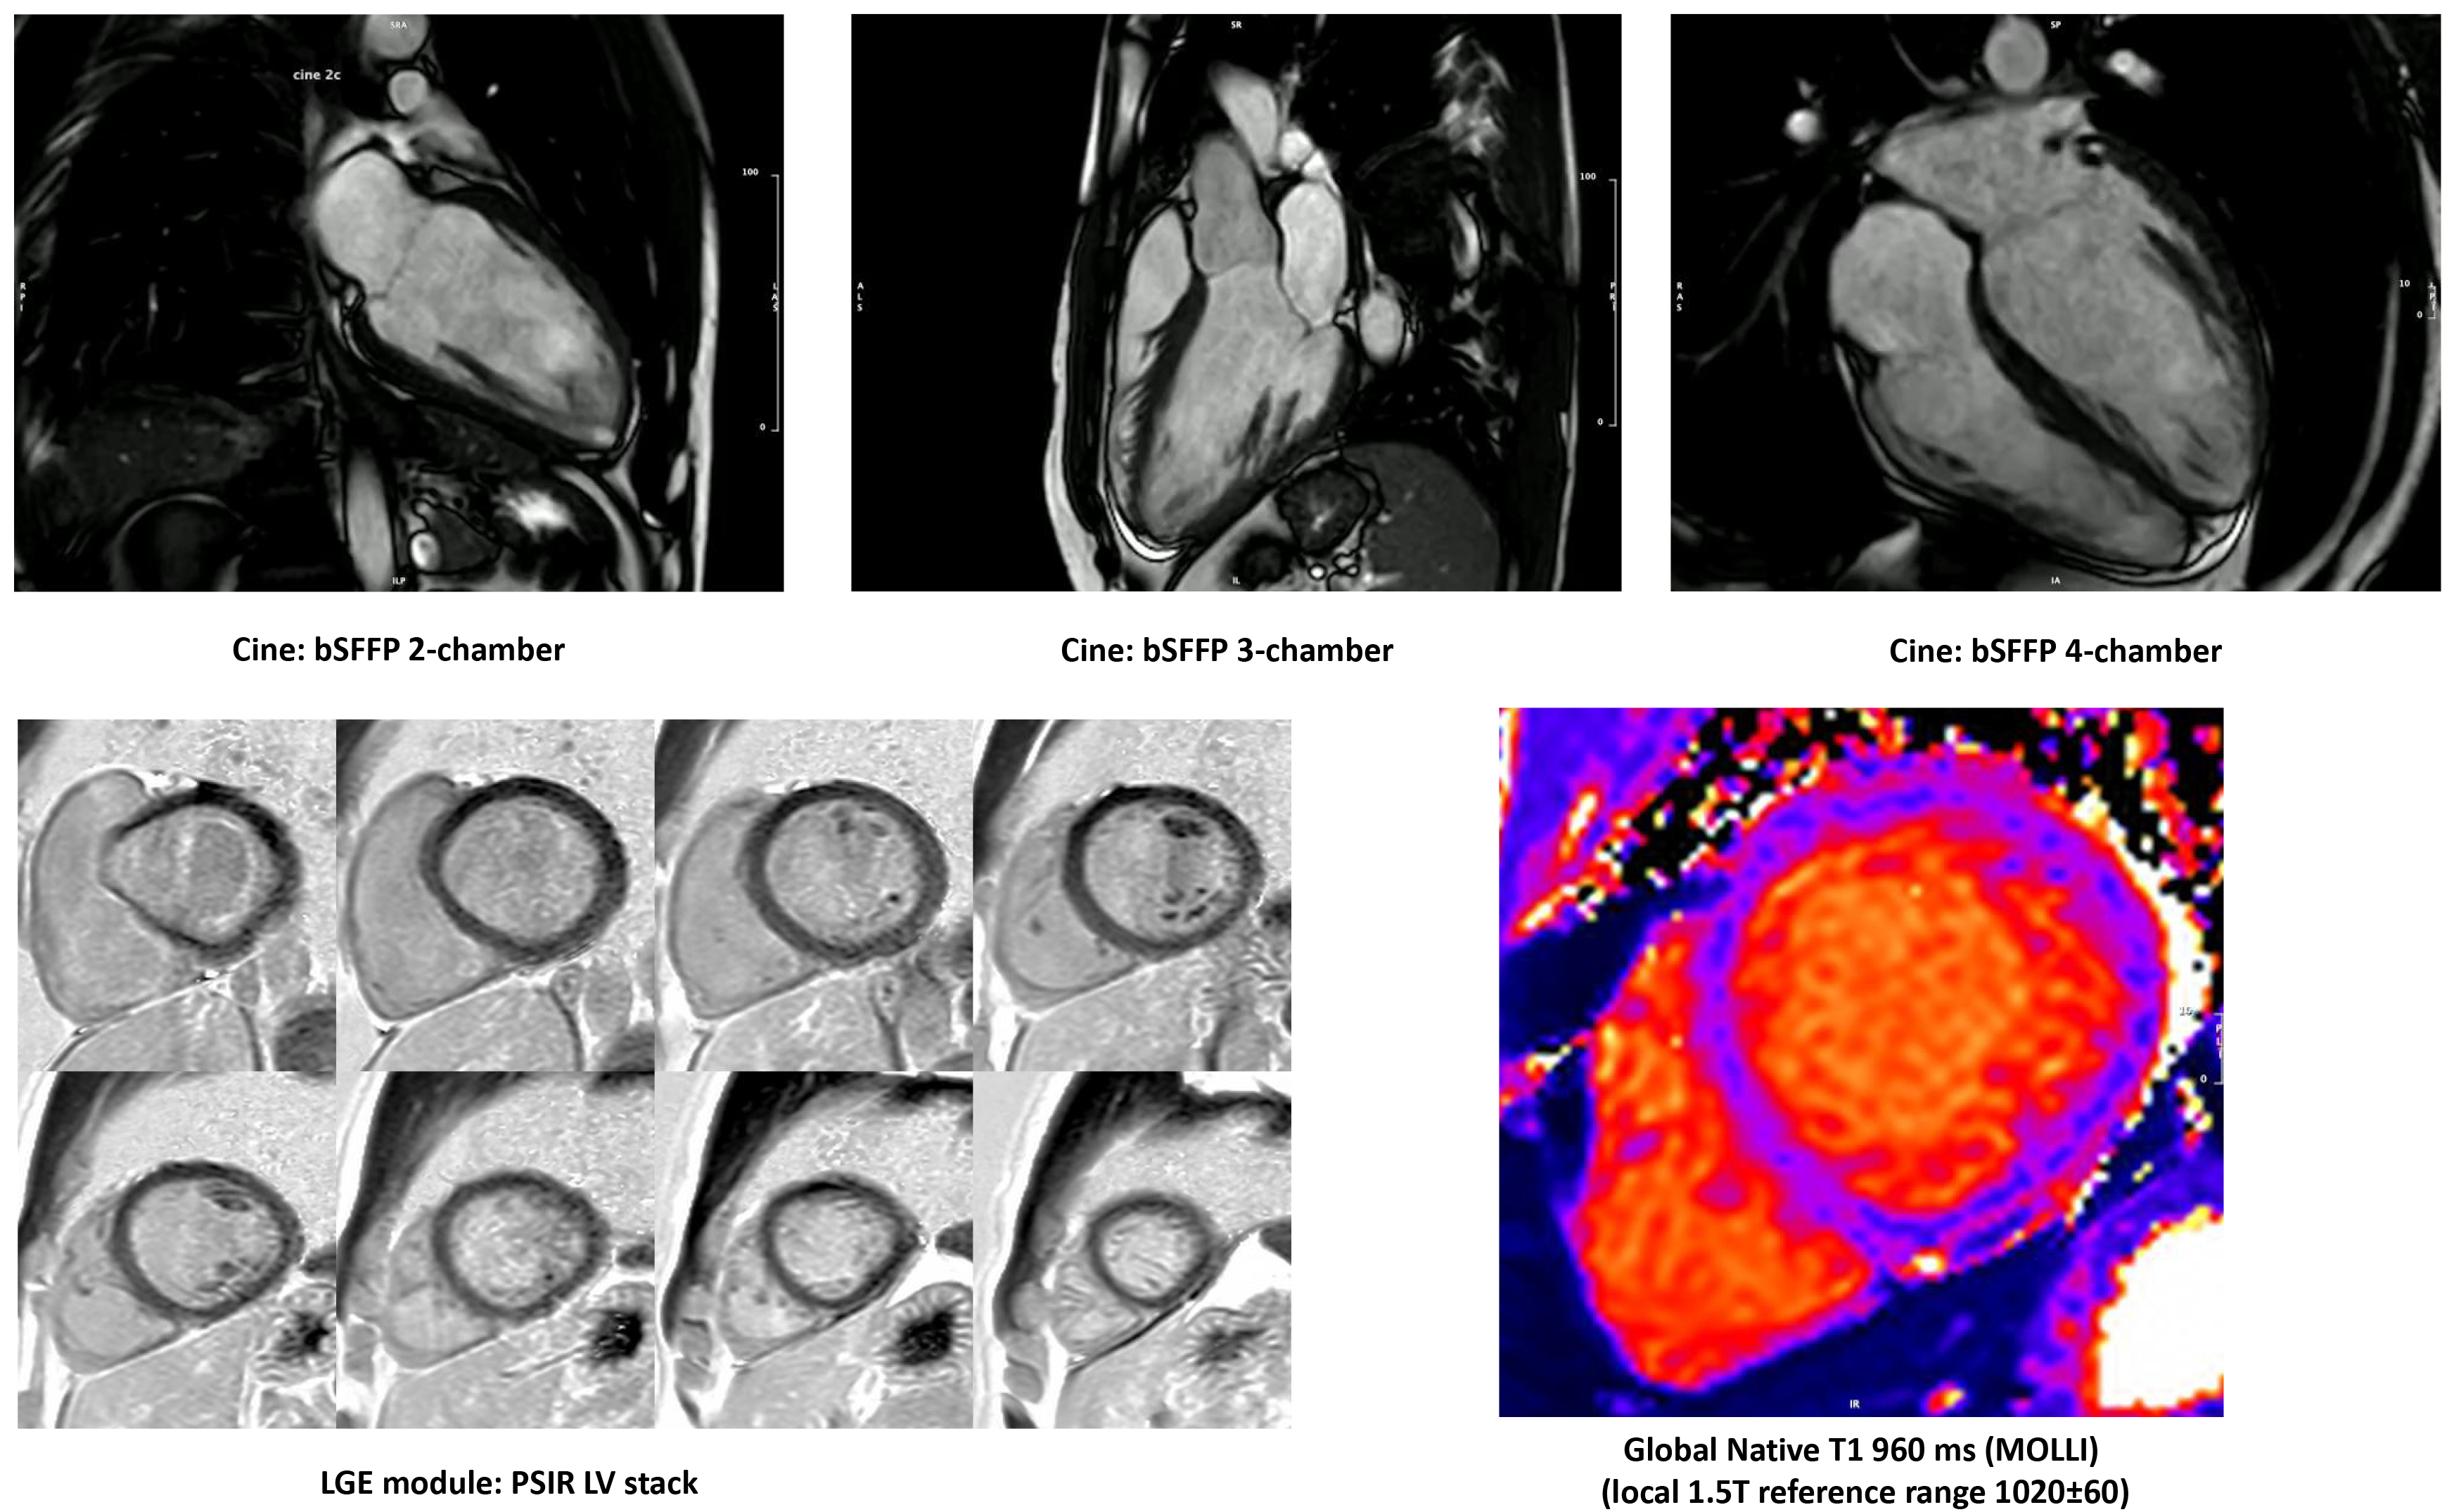

3.3.2 Cardiovascular Magnetic Resonance

CMR is an established imaging modality for the cardiovascular assessment of athletes. It is a third-tier diagnostic tool that helps to discriminate between physiology and pathology [65], and it is superior to echocardiography in differentiating athlete’s heart from structural and functional change [123]. The limitations of CMR include, among others, high cost, limited accessibility and claustrophobia, other than untested or low interobserver variability [124].

CMR is the gold standard for defining biventricular volumes and mass, and quantification of volumes and flow (Table 7, Ref. [125]) [126], providing advanced myocardial tissue characterization with excellent accuracy and precision. CMR has the incremental benefit of allowing tissue characterization by identifying myocardial inflammation and fat infiltration through T1 and T2 weighted images and mapping. CMR allows the detection of replacement fibrosis by late gadolinium enhancement (LGE) imaging, also pointing to the description of ischemic vs nonischemic patterns of myocardial damage [127]. As such, CMR supports the diagnosis of myocarditis and cardiomyopathies [128], such as HCM [129] and ACM [130, 131, 132, 133]. To differentiate between pathologic modification and physiologic remodeling, cardiac volumes and masses should always be compared to reference ranges deriving from CMR studies on healthy athletes [134], and adjusted to several factors, including type of sport, static and dynamic component, training hours per week, body surface area, age, gender, and ethnicity [135] (Fig. 4).

Fig. 4.

Cardiovascular magnetic resonance of an endurance athlete, investigated for premature ventricular beats and left ventricle (LV) dilatation and demonstrating balanced LV dilatation, borderline-low normal LV ejection fraction, no regional wall motion abnormalities, high-normal stroke volume, no late gadolinium enhancement, low-normal native myocardial T1, normal extracellular volume (25%).